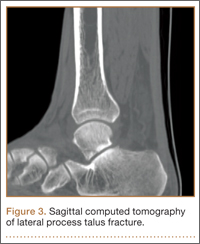

An increasingly common injury among snowboarders is a fracture of the lateral process of the talus; this injury accounts for 32% of snowboarders’ ankle fractures.6 The lateral process of the talus—wedge-shaped and covered in articular cartilage—is involved in the subtalar and ankle joints.9 A fracture here is often misdiagnosed as an ankle sprain (Figures 1–3).6,9,10 The exact mechanism of injury remains controversial, and several biomechanical factors seem to be involved. Funk and colleagues11 conducted a cadaveric study and concluded that eversion of an axially loaded, dorsiflexed ankle may be the primary injury mechanism for fracture. Furthermore, snowboarders have their feet in a position perpendicular to the board, and a fall parallel to the board could increase the eversion force on the ankle of the leading leg. Valderrabano and colleagues9 conducted a clinical study of 26 patients who sustained this injury from snowboarding. All the patients reported they had felt an axial impact from falling, jumping, or unexpectedly hitting a ground object, and 80% reported a rotational movement in the lower leg during the impact. The authors concluded that axial loading and dorsiflexion were not the only factors involved in lateral process talus fractures, and an external moment is necessary to cause this injury from a forward fall.9